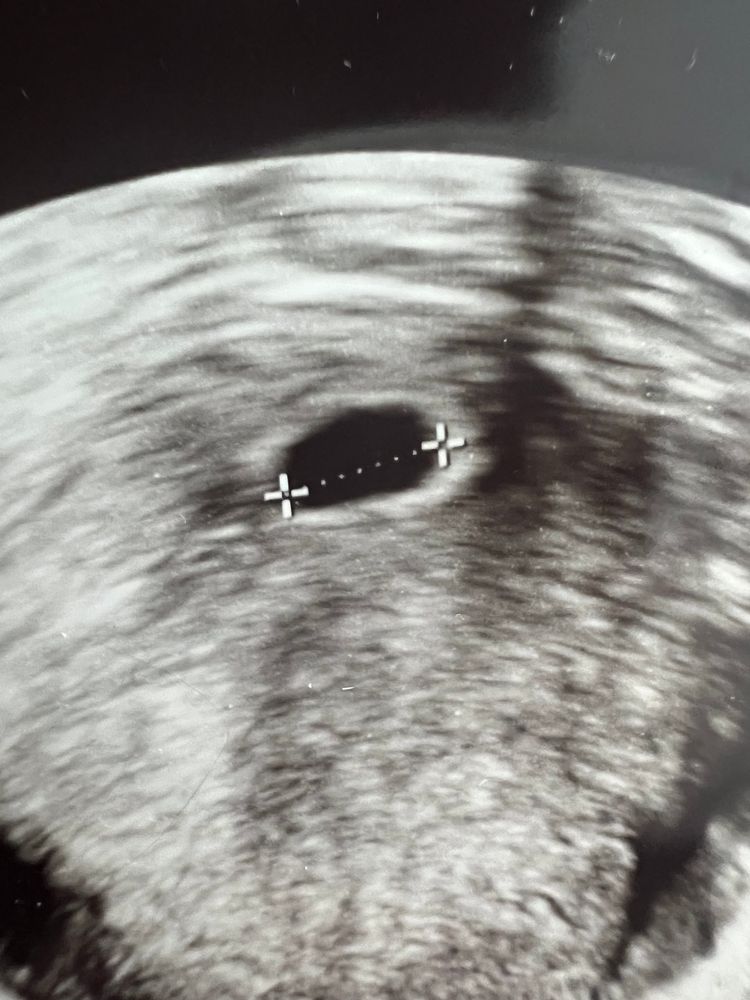

7 недель и 1 день акушерский срок. УЗИ выполнили, плодное яйцо 11 мм, но репродуктолог сказал, что плод не видно. Сказала приехать на контроль через неделю, но особо ни на что не надеяться, шанс очень маленький, что там что-то появится.

Вообще 11 мм это 5,5-5,6 где-то. На таком сроке часто не видно ни эмбрион ни даже жм

Oxxi, у меня эко. 14.03 оплодотворение, 19.03 подсадка 5ти дневного эмбриона. 8.04 это 20 дпп было узи, ПЯ меньше 5 мм. Вот за 10 дней оно выросло до 11 мм.